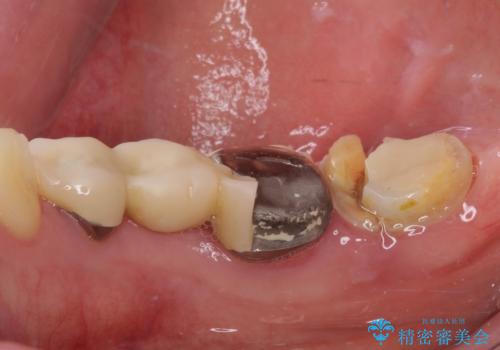

- 近医で奥歯が割れているので抜歯が必要と言われたとのことで来院された患者様です。

診断の結果、歯根が縦に破折しており抜歯が必要な状態でした。

抜歯してからインプラント埋入までには時間がかかるため、その間に下顎左右臼歯の金属のブリッジをオールセラミックへ変えていくこととしました。